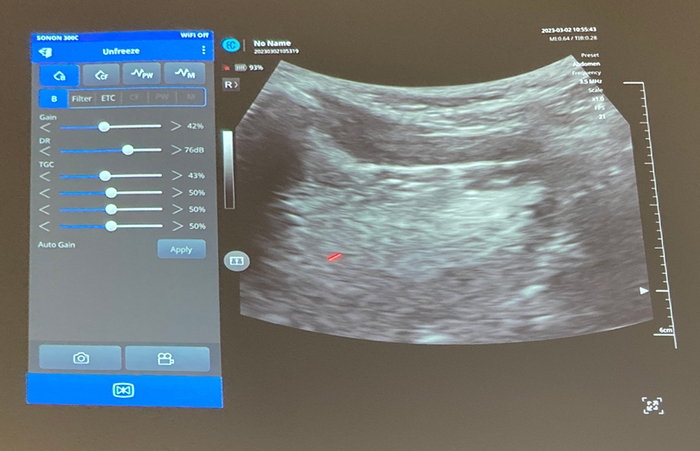

超音波(エコー)を使用し、飲み込み時の咽頭部周辺の筋肉の動きを数値化して評価します。検査における身体的負担が少なく、誰でも簡単・明確に摂食嚥下の状態を評価可能で、その評価に基づき、最適な「摂食嚥下機能改善プログラム」を個々に提供するシステムです。